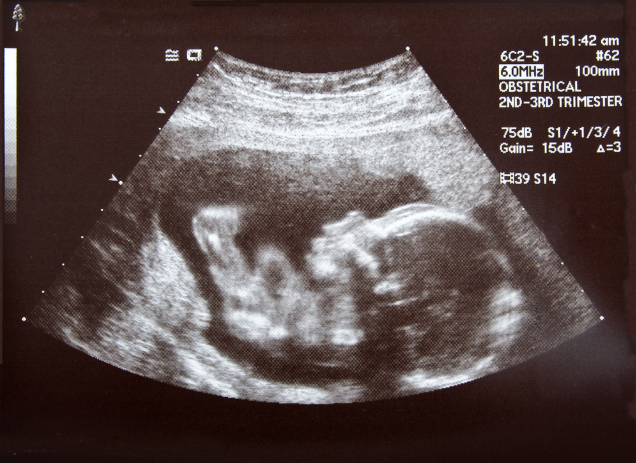

Hãy cùng chúng tôi tìm hiểu Những điều cần biết về siêu âm khi mang thai

Mỗi lần siêu âm có thể giúp bác sĩ xác định bạn đang ở giai đoạn nào của thai kì. Nó có thể xác nhận lại hoặc cho thấy thay đổi về ngày dự kiến sinh. Siêu âm có thể cho thấy giới tính, nhịp tim, nhịp thở, chuyển động và vị trí của thai nhi trong tử cung. Nhưng nếu thai nhi còn quá nhỏ, siêu âm khó có thể cho thấy những điều này. Siêu âm cũng có thể cho bạn biết nếu bạn mang đa thai.

Sóng âm gặp các cấu trúc cơ thể bạn và em bé sẽ bị phản lại và đầu dò cũng sẽ nhận những sóng âm phản xạ lại đó. Những sóng âm đó được sử dụng để tạo nên hình ảnh ở trên màn hình TV hoặc trên màn hình máy tính. Vùng trắng và xám trên hình ảnh thể hiện xương và các mô, vùng tối thể hiện các dịch, như nước ối xung quanh em bé. Bạn khó có thể nhận ra em bé trong hình ảnh nên bác sĩ hoặc kỹ thuật viên sẽ giải thích cho bạn các hình ảnh siêu âm cho thấy gì. Bạn có thể sẽ muốn lấy một vài bản siêu âm để đem về nhà. Xét nghiệm mất khoảng 20 phút hoặc lâu hơn.